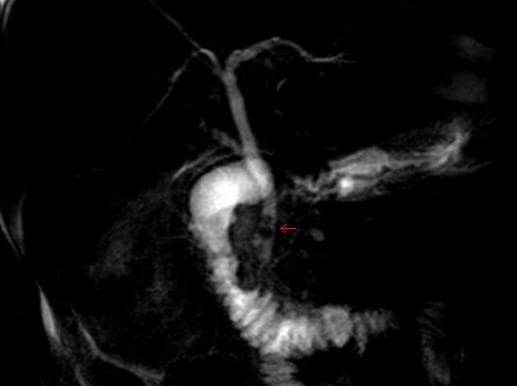

Common bile duct stone, also known as choledocholithiasis, is the presence of gallstones in the common bile duct (CBD) (thus choledocho- + lithiasis). This condition can cause jaundice and liver cell damage. Treatments include choledocholithotomy and endoscopic retrograde cholangiopancreatography (ERCP). Murphy's sign is commonly negative on physical examination in choledocholithiasis, helping to distinguish it from cholecystitis. Jaundice of the skin or eyes is an important physical finding in biliary obstruction. Jaundice and/or clay-colored stool may raise suspicion of choledocholithiasis or even gallstone pancreatitis. If the above symptoms coincide with fever and chills, the diagnosis of ascending cholangitis may also be considered. More than 70% of people with gallstones are asymptomatic and are diagnosed incidentally during ultrasound. Studies have shown that 10% of those with gallstones will develop symptoms within 5 years of diagnosis, and 20% within 20 years. While stones can frequently pass through the common bile duct into the duodenum, some stones may be too large to pass through the common bile duct and may cause an obstruction. One risk factor for this is duodenal diverticulum. This obstruction may lead to jaundice, elevation in alkaline phosphatase, increase in conjugated bilirubin in the blood and increase in cholesterol in the blood. It can also cause acute pancreatitis and ascending cholangitis. Choledocholithiasis (stones in common bile duct) is one of the complications of cholelithiasis (gallstones), so the initial step is to confirm the diagnosis of cholelithiasis. Patients with cholelithiasis typically present with pain in the right-upper quadrant of the abdomen with the associated symptoms of nausea and vomiting, especially after a fatty meal. The physician can confirm the diagnosis of cholelithiasis with an abdominal ultrasound that shows the ultrasonic shadows of the stones in the gallbladder. Although unusual, it is possible to have a common bile duct stone despite prior cholecystectomy.